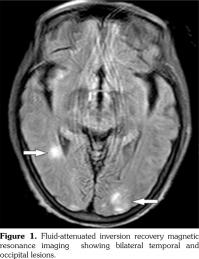

Posterior reversible encephalopathy syndrome (PRES) is known as reversible posterior leukoencephalopathy syndrome, primarily portrayed in 1996.(1) It is characterized by headache, vomiting, seizure, confusion, and visual disturbance. The brain magnetic resonance imaging is the diagnostic gold standard showing edema in the white matter of bilateral temporal, parietal, and occipital lobes for neuroradiologic characteristics, totally reversible.(2) To our knowledge, this is the first report of an elderly female patient of PRES complicated with systemic lupus erythematosus (SLE), Sjögren syndrome (SS), and primary biliary cirrhosis (PBC).

A 65-year-old female patient was admitted because of upper extremity shaking and lower extremity weakness for one day, fatigue, and anorexia for more than two months. She was firstly suspected of Parkinsonian syndrome. Levodopa and benserazide hydrochloride tablets were administered. However, her condition deteriorated aggressively, and it was hard for her to walk. Meanwhile, there were no complaints of rash, oral ulcer, baldness, arthritis, or photosensitivity. She denied headache, dizziness, vomiting, confusion, or double vision. Interestingly, she suffered from dry mouth and dry eyes for several months. She had never smoked or consumed alcohol, or received any suspected drugs. Physical examination was significant for fractured teeth and decreased myodynamia with 4/5 strength of upper extremity and 2/5 strength of lower extremity symmetrically. Laboratory tests revealed elevation of the 24-hour urine protein (1.20 g), positive autoantibodies (antinuclear antibody, anti- Smith, anti-double stranded deoxyribonucleic acid antibody) and decreased complement. SLE was diagnosed.(3) The positive tests of anti-Sjögren syndrome A antibody and Schirmer test, ocular staining score (>3) combined with clinical symptoms supported the diagnosis of SS,(4) but the patient refused labial salivary gland biopsy. Furthermore, PBC was diagnosed according to her raised alkaline phosphatase and positive serum anti-mitochondrial antibodies, excluding other causes of cholestasis. However, she rejected liver biopsy. Magnetic resonance imaging of the brain revealed symmetrically patchy lesion involving predominantly the subcortical white matter of the bilateral temporal and occipital (Figure 1). Therefore, she was ultimately diagnosed with PRES, SLE, SS, and PBC. Treatment was initiated immediately, including methylprednisolone 80 mg once a day, cyclophosphamide 400 mg∞3 days, plasmapheresis, and hypotensor. Several days later, her clinical symptoms improved greatly. Repeated magnetic resonance imaging was performed two months later, showing that the lesion had almost disappeared. Urinary protein proved to be 0.06 g/24 hour in follow-up. A written informed consent was obtained from the patient.

Compared to SS and PBC, PRES in SLE patients is relatively frequent. Younger age is independently associated with PRES episodes in patients with SLE and the mean±standard deviation age (years) is 27.9±1.1.(5) However, our patient was older. Besides, the lesion was different from conventional lupus encephalopathy, which frequently occurs in frontal lobe and parietal lobe. The underlying pathophysiology of PRES complicated with autoimmune diseases are as follows: theories including dysfunction of autoregulatory cerebral perfusion mechanisms and endothelia, inflammasome activation of interleukin-18 and neutrophil extracellular trap formation and the presence of autoantibodies (N-methyl-D-aspartate receptor and anti- aquaporin 4) were studied.(6-9) Recent genome- wide studies have pointed out that risk loci, such as interferon regulatory factor 5-transportin-3 may be associated with the genetic susceptibility to both SLE and PBC.(10) Osteopontin, recognized as one of the spontaneous autoimmune models of SLE, may also be related.(11) Although the majority of patients have active disease and are on immunosuppressive therapy prior to developing PRES, they still require an increase or continuation of their immunosuppressive therapy to control disease activity after the onset of PRES.